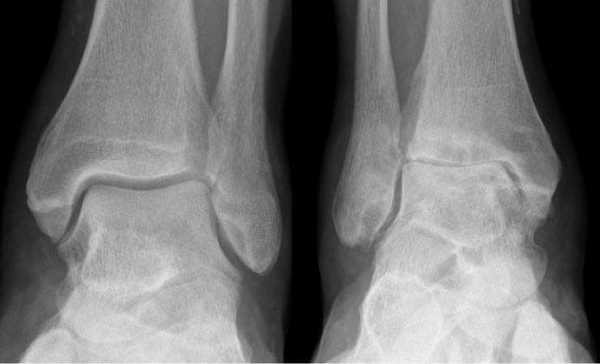

Артроз левого сустава. Суставная щель очень мала.

Добавочная ладьевидная кость классифицируется в соответствии с рентгенологическими ее особенностями:

- Сесамовидная косточка в толще сухожилия задней большеберцовой мышцы в области его прикрепления к ладьевидной кости

- Добавочная ладьевидная кость, сочленяющаяся синхондрозом с ладьевидной костью

- Костный выступ ладьевидной кости

Рентгенограмма стопы при 1 типе добавочной ладьевидной кости

Рентгенограммы стоп: 3 тип добавочной ладьевидной кости